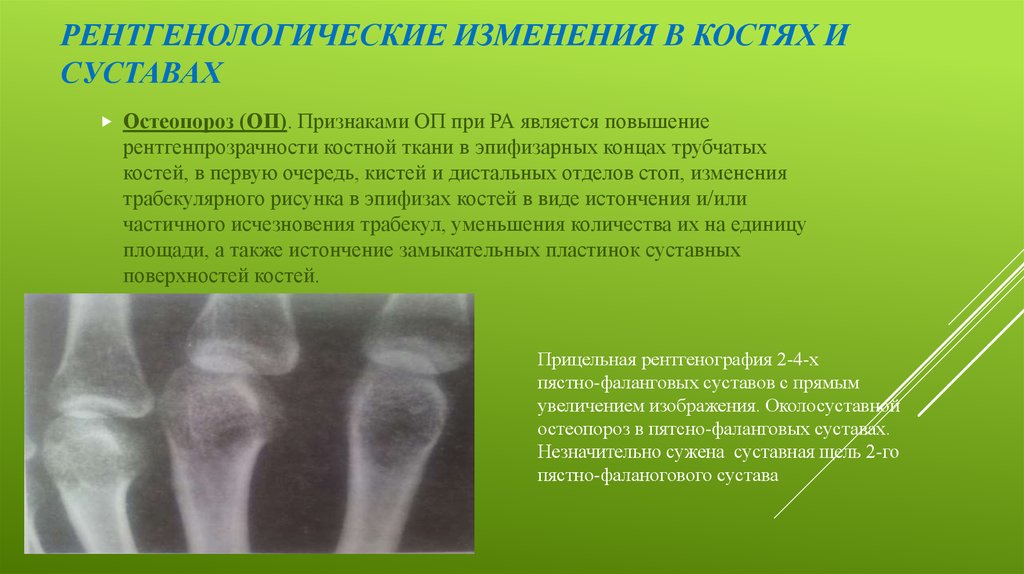

Коленные суставы и ревматоидный артрит: фото и информация